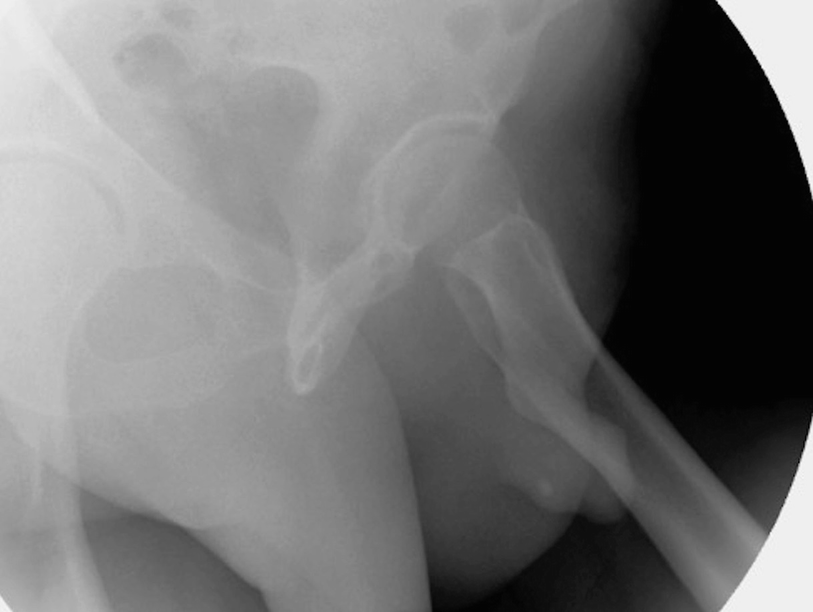

5.3.2 Retrograde Urethrogram and Voiding Cystourethrogram

Proper positioning for retrograde urethrogram. In particular, note the occlusion of the downward left obturator fossa. Also, an incidental urethral stone is also evident